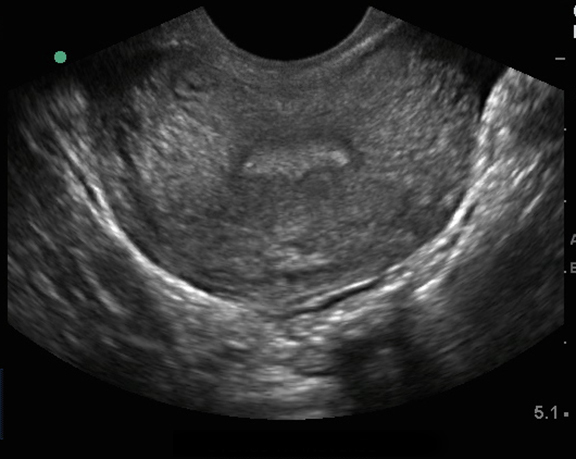

Image : Échographie pelvienne endovaginale, coupe transverse de l'utérus

Coupe transverse de l'utérus